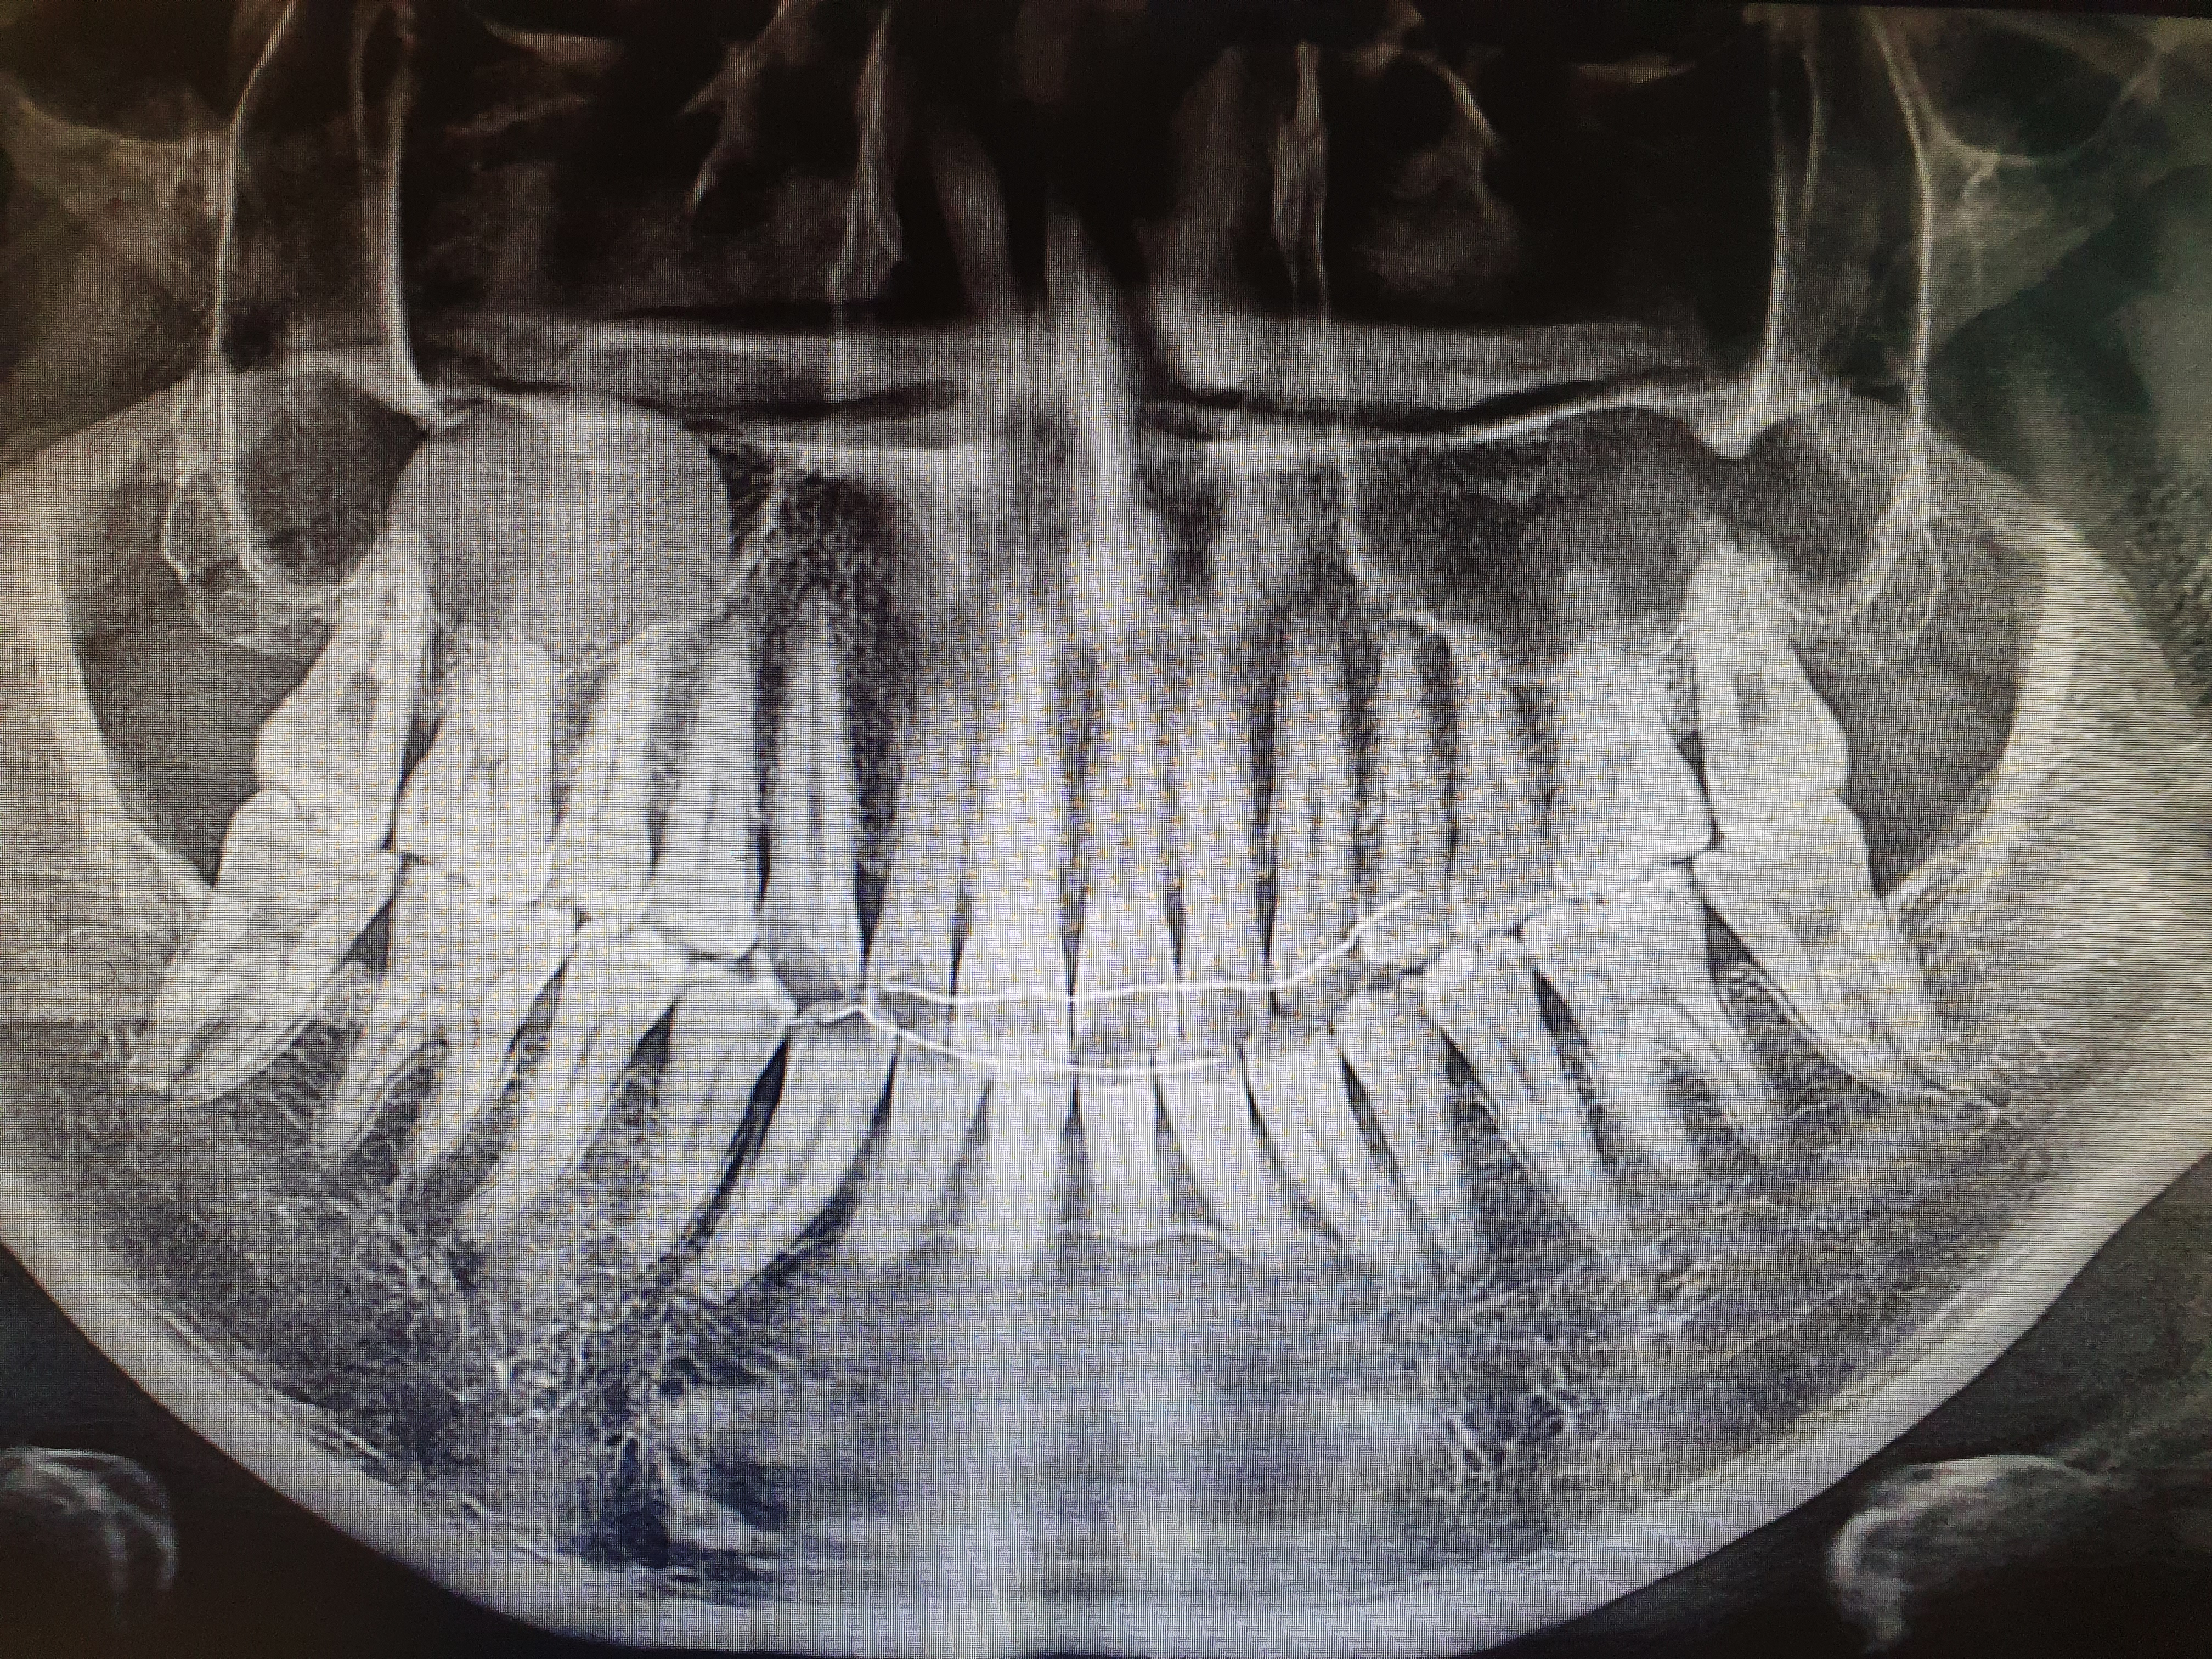

안 그래도, 지난 진료 때 여차하면 '치료' 차원에서 구강 '편평태선'을 잘라낼 수도 있다는 말씀을 하긴 하셨는데, 간단한 시술이라도 막상 닥치니 겁이 좀 나긴 나더라. 구강 '편평태선' 시술 진행은 다음과 같다. (1) 시술 부위 마취 (2) 편평태선 제거/절제 (3) 절제 부위 봉합 (4) 주변 레이저 치료 (5) 지혈

수술이 다 그렇지만, 이런 간단한(?) '시술'로도 몸에 오한이 찾아와 첫날이 가장 힘들었다. 둘째날부터 조금이나마 '죽'도 먹고 '양치'도 할 수 있어 그나마 살만했던 것 같다. 입을 벌려 안을 들여다보면, 좌우 양 볼 안쪽에 시술로 인해 봉합된 모습이 매우 충격적이라며... 그렇게 시술로 잘라낸 일부는 '조직검사' 해볼 거란다. (제발, 아무 이상 없기를!)